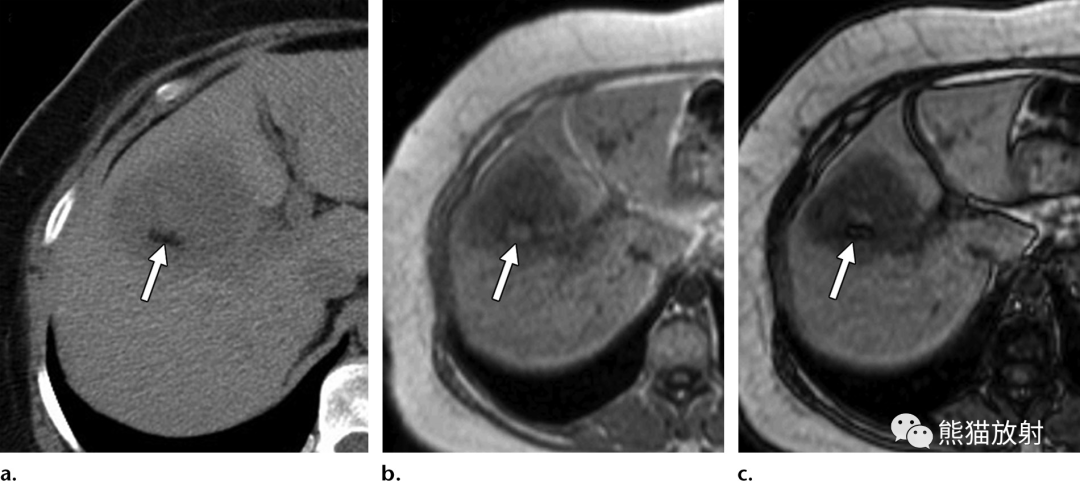

69岁男性,胆总管结石患者,发热,实性机化性肝脓肿。(a) 动脉早期CT图像显示具有“靶征”表现的结节,中心早期强化,与肝实质相似,边缘密度较低。(b) 延迟期病灶中心呈等密度,外周环状强化(箭头)。由于脓液吸收而无中心液体内容物,使脓肿呈实性外观,可能难以与肝内胆管细胞癌相鉴别。